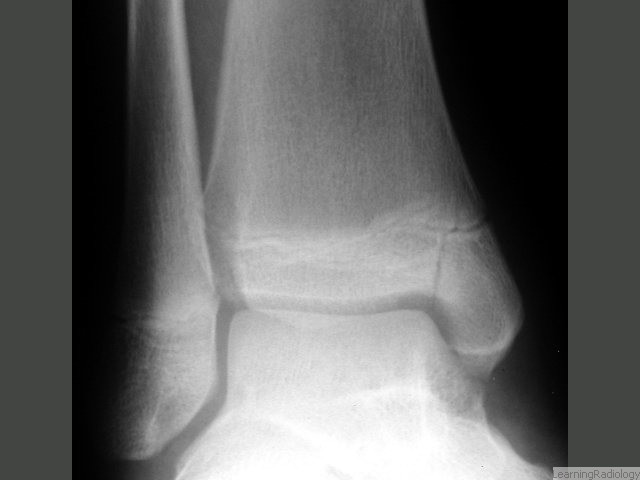

What type of Salter Harris is this?

Type 4 - involves all 3 parts